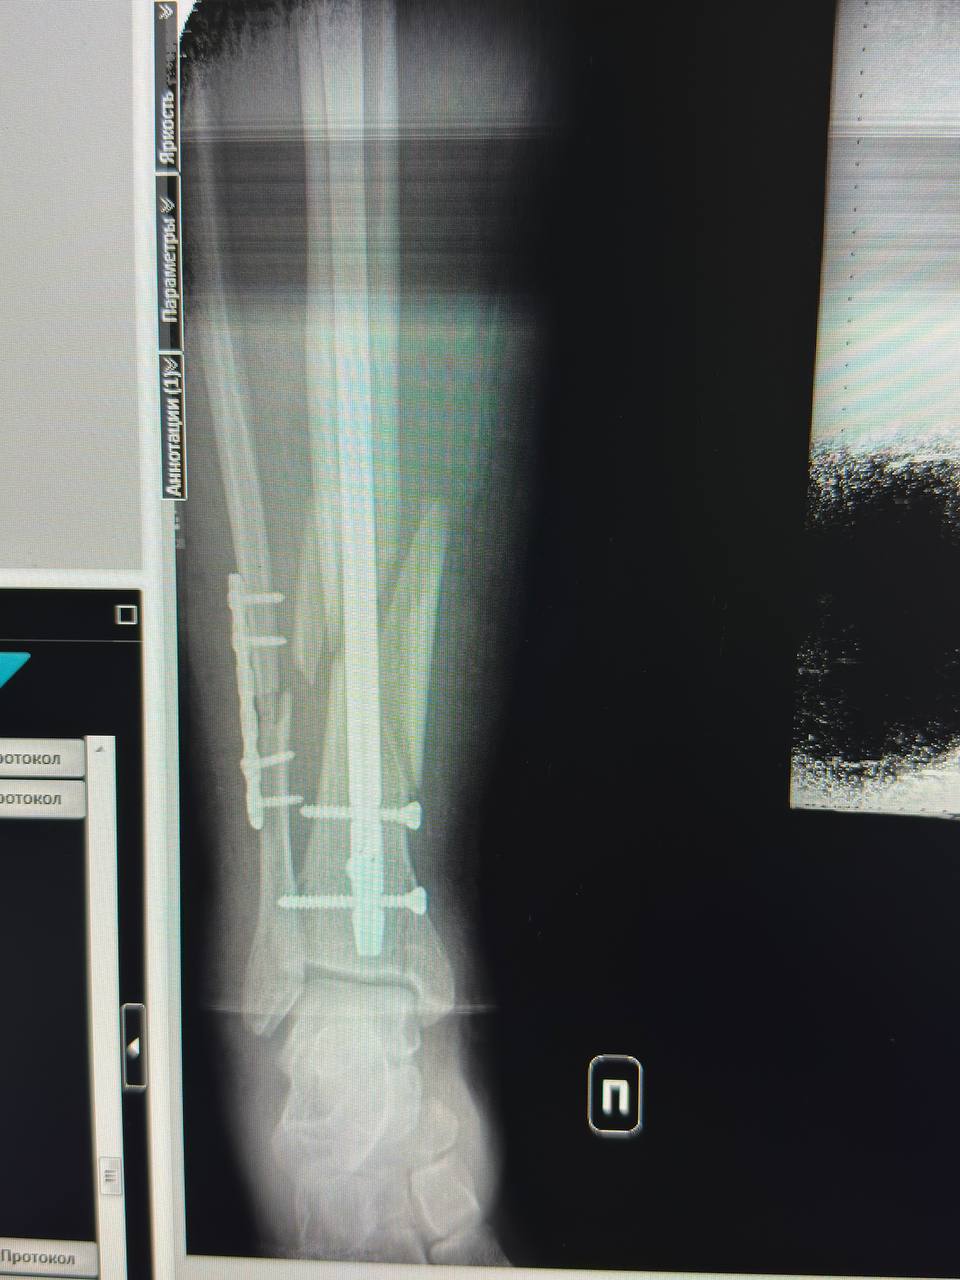

Сломала ногу. Перелом большой и малой берцовой кости. В данный момент лежу в больнице, о чуде на нг можно и не мечтать.... Я мать одиночка с неблагополучной семьи. Так что помощи ждать не откуда. Реабилитация от 3 до месяцев. Соответственно работать не смогу. Прошу помощи как материальной, так и может кто знает куда можно обратиться за помощью. Нужны будут продукты и оплата коммунальных услуг. А также деньги на транспортировку меня.Данные скрыты номер карты моего сына Димы. Буду благодарна любой помощи....PS может кто поможет с работой на удалёнке.